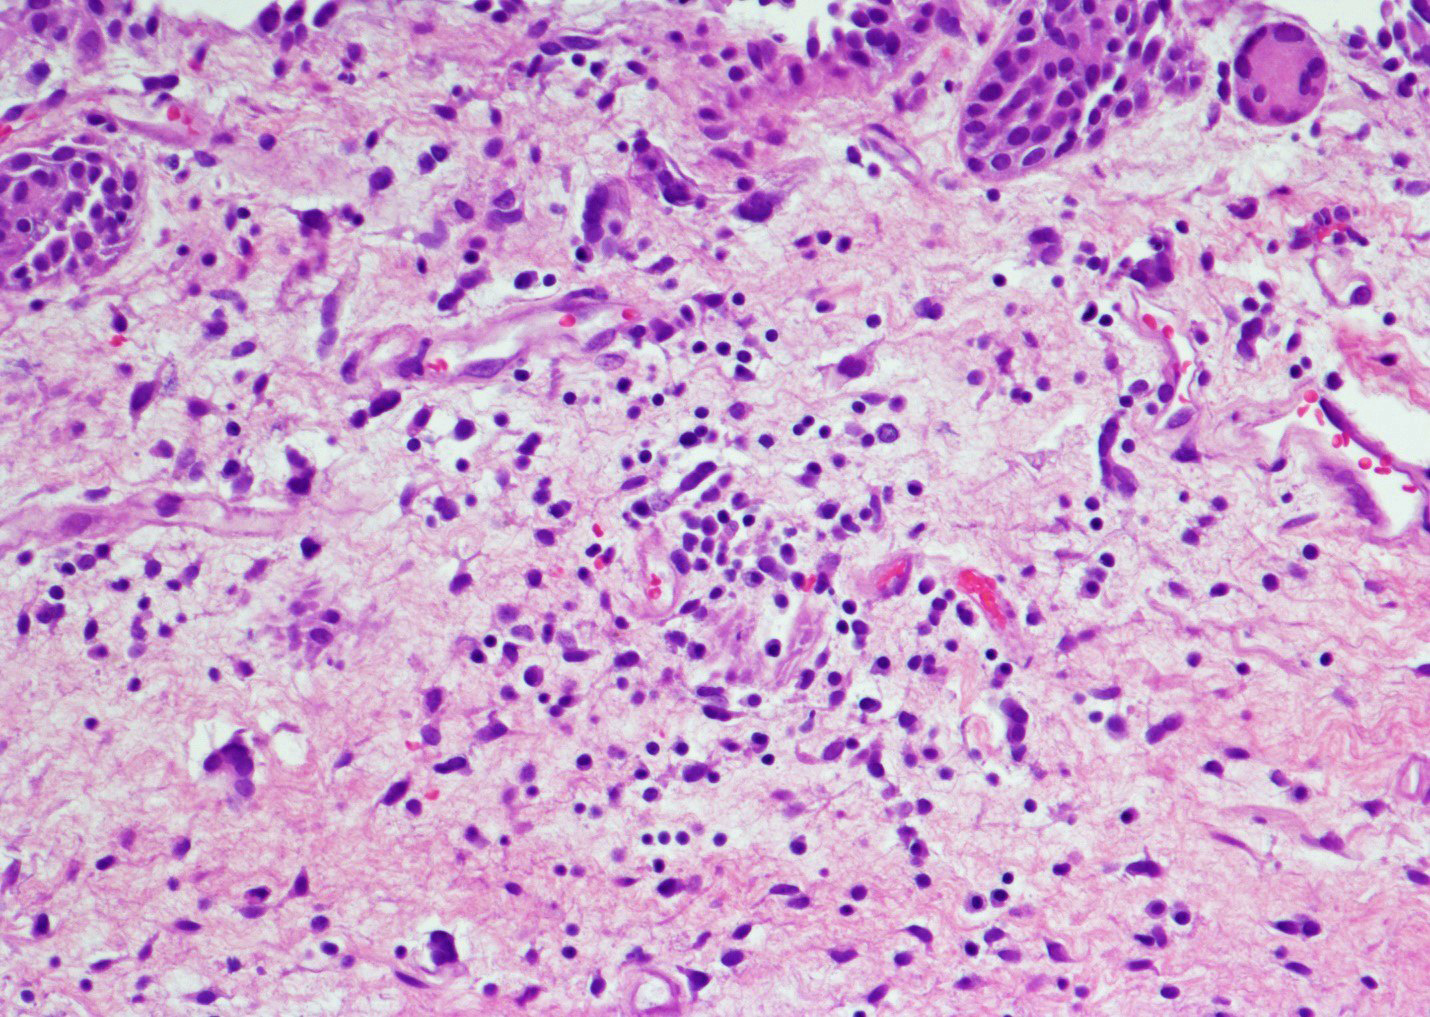

Microscopic (histologic) description

- Vessels with fibrin thrombi, fibrinoid vascular necrosis, vascular congestion, thickened walls, endothelial proliferation and telangiectasia

- Acute and chronic inflammation

- Reactive multinucleated stromal fibroblasts with smudgy nuclei

- Fibrosis and edema

- Hemorrhage and hemosiderin

- Acute phase: edematous, congested and telangiectatic vessels, acute and chronic inflammatory infiltrate, atypical stromal cells with multinucleated forms

- Chronic phase: atrophic urothelium, atrophic smooth muscle layer, collagen deposition (fibrosis) (Am J Surg Pathol 2004;28:909)

Microscopic (histologic) images

Contributed by Y. Albert Yeh, M.D., Ph.D. and Jennifer Lee, M.D.